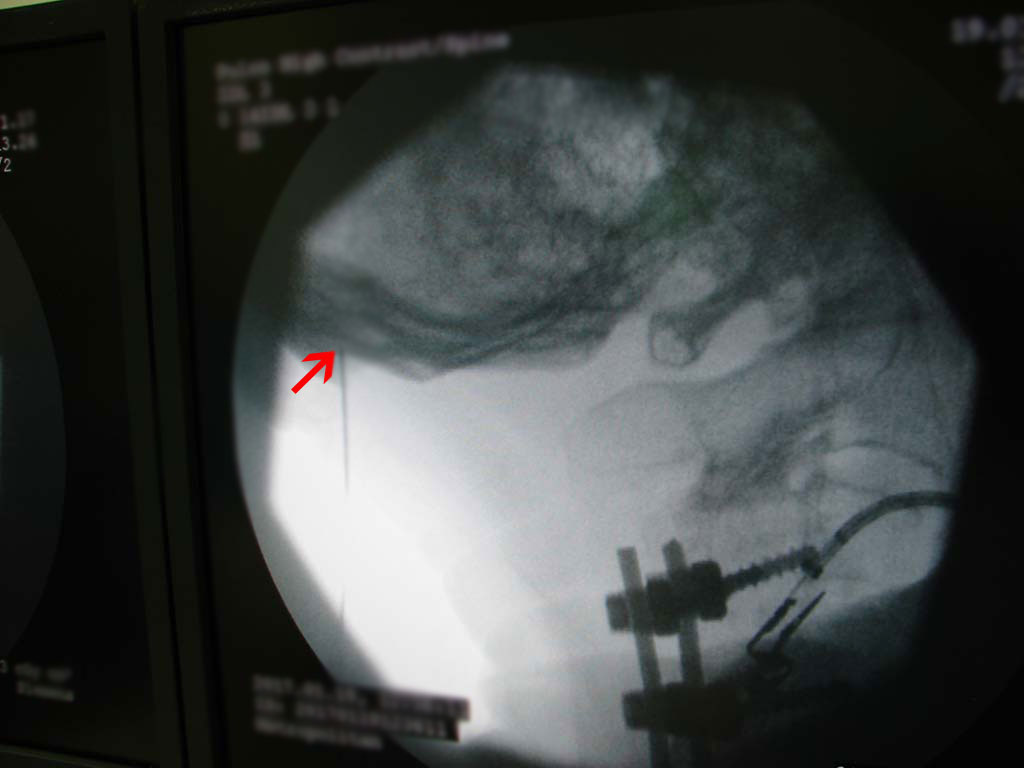

- Επίπεδο A2-A3